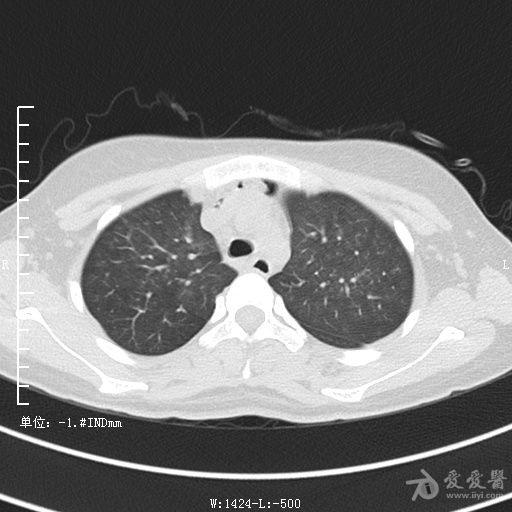

典型支气管扩张及肺水肿CT片

典型支气管扩张肺水肿